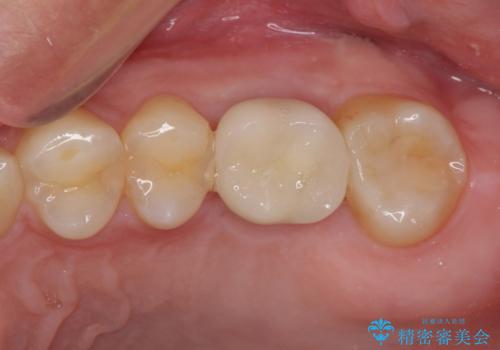

- 深い咬み合わせと前歯のデコボコ、奥歯の欠損を気にして来院された患者様です。

歯列矯正はインビザラインを使用し、矯正治療中の適切な時期に奥歯の欠損部位にインプラントを埋入することとしました。

矯正治療とインプラント治療を同じ歯科医師が担当することで、通常見られるような複数医院を行き来する煩雑さや、複数担当医の見解の違いによる治療の遅滞といった煩わしさは一切なく、スムーズに治療を進めることができました。

安定して咬めるようになり、患者様には大変満足していただきました。